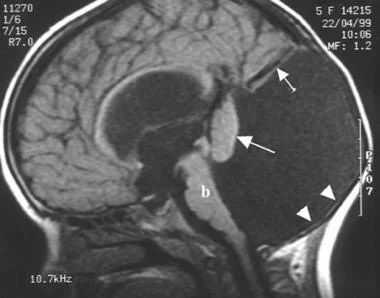

- Классический тип аномалии — задняя черепная ямка расширена, четвертый желудочек кистозно изменен, червь мозжечка частично или полностью недоразвит, полушария его гипоплазированы, а намет находится выше, чем в норме, желудочковая система не сообщается с подпаутинным пространством, часто наблюдаются мозговые кисты и отсутствие мозолистого тела, практически у всех пациентов есть гидроцефалия, возможно сдавление стволовых структур. Порок проявляется клинически уже с рождения и имеет неблагоприятный прогноз.

- Вариант Денди-Уокера — морфологические признаки выражены меньше, чем при классической форме, гипоплазирован нижний отдел червя мозжечка, желудочки сообщаются с кистой и ликворными пространствами, обеспечивая отток ликвора, поэтому гидроцефалия наблюдается редко. Задняя черепная ямка имеет нормальные размеры, стволовые структуры не сдавливаются.

- Киста кармана Блейка — расширение желудочковой системы с гидроцефальным синдромом, киста расположена под или за мозжечком, червь развит относительно хорошо. Четвертый желудочек расширен, но не сообщается с затылочной ликворной цистерной.

- МРТ для определения анатомических особенностей четвертого желудочка мозга;